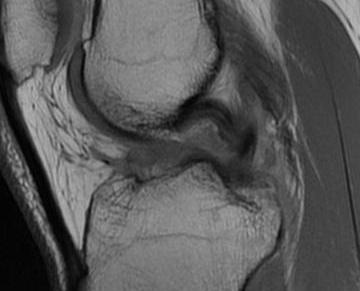

MRI

PCL completely torn

PCL midsubstance tear with lengthening

Apparent ACL laxity due to PCL tear and posterior tibial sag; ACL tension restored with anterior drawer